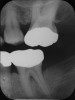

Locally delivered, controlled-release agents are a popular treatment adjunct and serve to augment scaling and root planing to help improve outcomes. Clinical studies have shown that use of such agents can provide an average of 0.5-mm additional pocket depth reduction over scaling and root planing alone, so the practitioner must weigh the cost-benefit ratio of using these products in each patient situation.39,40 A guideline for the appropriate use of locally delivered antimicrobials has been provided by the American Academy of Periodontology.41 These materials are contraindicated in patients with (1) multiple 5-mm pocket depths in one quadrant; (2) anatomic defects caused by periodontal diseases (intrabony defects); and (3) when the previous use of locally delivered agents has failed to control disease. As noted before, a follow-up reevaluation always should be completed to evaluate the success of any therapeutic intervention, generally at 4 to 6 weeks after treatment has been rendered30,31 (Figure 3A through Figure 3D).

Figure 3a   patient in posttreatment periodontal maintenance program returned with (A) isolated bleeding on probing;

Figure 3a

Figure 3b   patient in posttreatment periodontal maintenance program returned with (B) a 5-mm probing depth noted at a maintenance visit.

Figure 3b

Figure 3c  The site was treated by localized scaling and root planing, followed by use of Arestin (minocycline microspheres).

Figure 3c

Figure 3d  The resolution of inflammation and bleeding on probing on the reevaluation appointment 6 weeks later.

Figure 3d